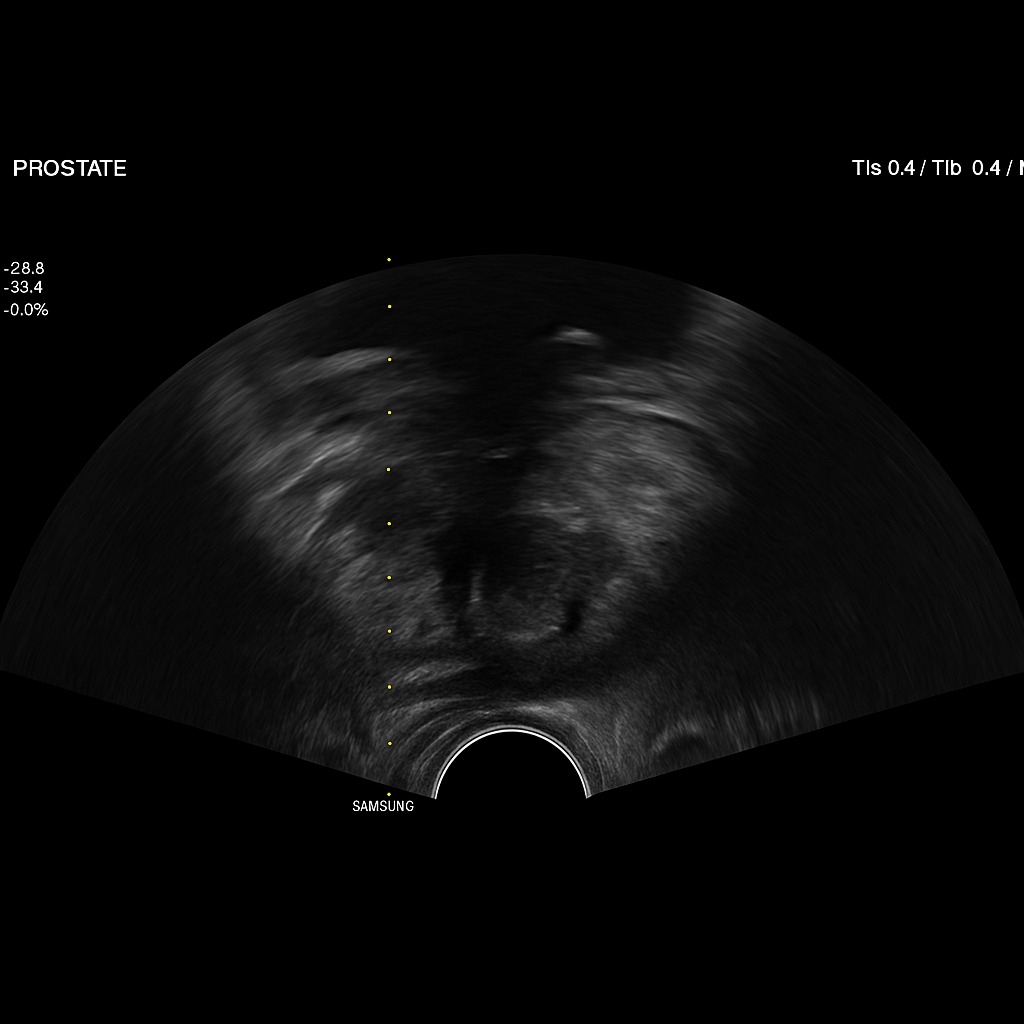

Prostate Biopsy

전립선 조직검사는 전립선에서 실제 조직 샘플을 채취하여 현미경으로 분석하는 검사입니다.

전립선에 발생한 종양, 염증, 이상 변화 여부를 정확하게 확인할 수 있는 확진 검사로,

전립선암 여부를 최종적으로 판단하는 데 필수적인 검사입니다.